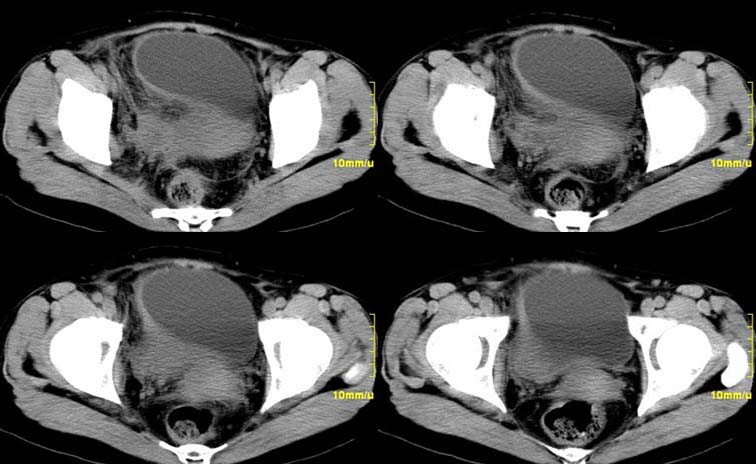

患者,52,右下腹疼痛一月,当时有发热,抗炎治疗20余天,至今仍疼痛,且有低热。

增强

右侧附件见一肿块,边缘与周围组织分界不清,增强扫描见肿块明显强化,越到后期强化越明显,中央见坏死,内壁光整,与临近子宫壁、直肠及膀胱后壁均见炎症波及。这种厚壁肿块、内缘光整外缘模糊、增强扫描强化越后越强是附件脓肿典型的ct表现。

右侧卵巢输卵管慢性脓肿,炎症波及临近子宫、直肠及膀胱形成粘连。

病变定位在右侧附件,肿块内见有低密度灶,周围结构模糊,增强肿块实质部分明显强化,因患者起病有发烧,故首先考虑右侧附件炎性包块并脓肿形成,不除外以实质部分为主的不典型卵巢癌的可能。